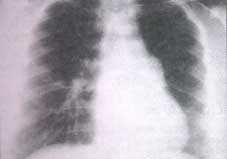

Radiografía del tórax

La radiografía del tórax (figura N° 7) tomada al ingreso mostraba asimetría de los campos pulmonares por menor tamaño pulmonar izquierdo y disminución de sus marcas vasculares. La imagen de crecímiento del tronco de la arteria pulmonar sugería hipertensión pulmonar.

Observaciones en la radiografía tórax

En la radiografía del tórax de estos pacientes se observa ausencia de la imagen de la arteria pulmonar, disminución de las marcas vascu lares, hemitórax ipsilateral de menor tamaño con desplazamiento mediastinal y elevación del hemidiafragma.